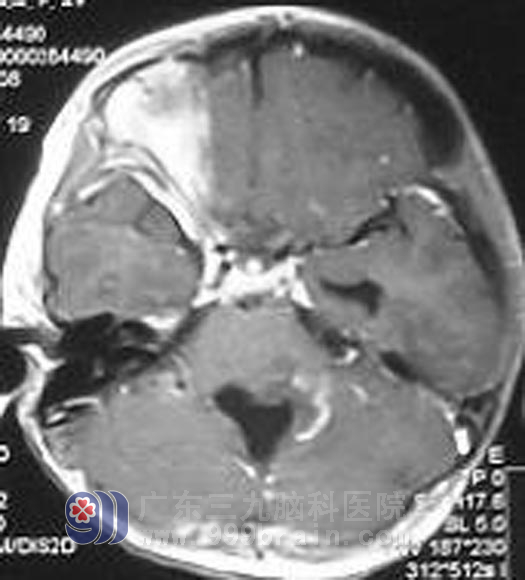

手术后

莹莹是广东兴宁的农村里可爱的小女孩,2006年10月就在莹莹刚满4岁的时候,小莹莹无征兆出现恶心呕吐,伴有头晕头痛,父母带着莹莹到当地最大的医院就诊,头颅CT显示为小脑蚓部占位,并伴梗阻性脑积水。焦急的父母立即带着莹莹到了广州的大医院治疗,很快小莹莹接受了颅脑手术,因为病理是毛细胞性星型细胞瘤WHOI级,归属于良性肿瘤,且手术后莹莹的恶心呕吐头痛头晕症状都消失了,小莹莹没有接受肿瘤的进一步放疗。之后也没有遵医嘱定期复查。不曾想到的是,手术后残留的肿瘤细胞还在小莹莹的颅内生长、繁殖、肆虐着。http://www.999brain.com/